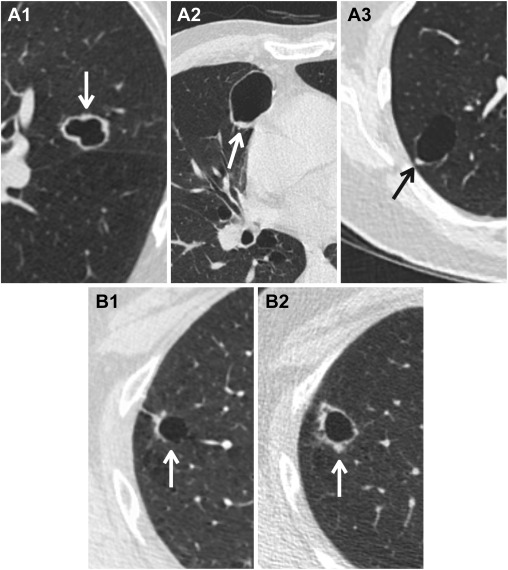

- Nang thành dày là nang đơn ngăn có độ dày thành 2 mm trở lên, có thể đồng nhất, không đối xứng, hoặc biểu hiện dưới dạng nốt thành khu trú (Hình 2).

Hình 2. Nang khí phổi không điển hình: thành dày. (A) Nang phổi có độ dày thành ≥ 2 mm là “thành dày” (mũi tên) và được phân loại và quản lý trong Lung-RADS v2022. Độ dày thành có thể là chu vi (A1), không đối xứng (A2) hoặc khu trú (A3). Nang thành dày được phân loại là Lung-RADS 4A. (B) Một bệnh nhân 62 tuổi khi sàng lọc CT ban đầu với một nang thành dày (mũi tên, B1)—Lung-RADS 4A. Nốt ổn định sau 3 tháng theo dõi và quay lại sàng lọc hàng năm theo quản lý Lung-RADS v1.1. Khi sàng lọc hàng năm, nang phổi không điển hình đã tăng kích thước với độ dày thành tăng và có nốt mới (mũi tên, B2). Bệnh nhân đã được phẫu thuật cắt bỏ và được chẩn đoán xác nhận là ung thư biểu mô tuyến. Trong Lung-RADS v2022, các nang có thành dày với độ dày thành ngày càng tăng hoặc có dạng nốt thành được phân loại là Lung-RADS 4B.